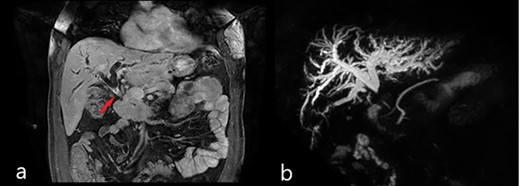

Abdominal US showed diffuse dilatation of the biliary tree. Magnetic resonance imaging and magnetic resonance cholangiopancreatography highlighted a 6-cm-long concentric thickening of the MBD below the biliary confluence towards the papilla of Vater (Fig. 1). Staging computed tomography (CT) showed no signs of lung or liver metastases (Fig. 2a). During percutaneous cholangiography, biopsies were performed, and a percutaneous internal-external drainage left in place to palliate jaundice. An 18-Fluorodeoxyglucoose Positron emission tomography (18-FDG-PET/CT) confirmed a slight uptake at the thickening of the MBD (Fig. 2b). Oncological markers, carcinoembryonic antigen and carbohydrate antigen 19-9 were not elevated.

Magnetic resonance imaging (MRI): (a) coronal scan showing the dilatation of bile ducts and the thickening of the MBD (red arrow); (b) magnetic resonance cholangiopancreatography (MRCP) showing the dilatation of intrahepatic bile ducts and the absence of signal from the MBD below the confluence to the papilla of Vater.